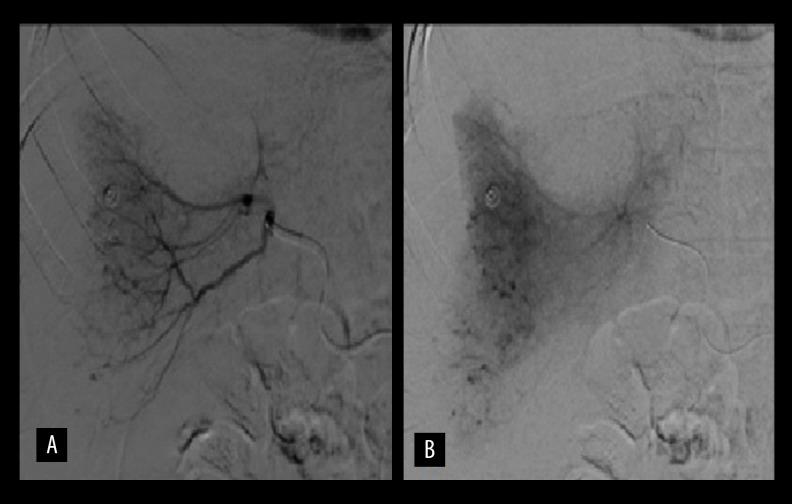

BACKGROUND Gastrointestinal stromal tumors (GISTs) are rare gastrointestinal neoplasms. The spontaneous rupture of a jejunal GIST is very rare and spontaneous rupture of liver metastasis from an intestinal GIST is even rarer with only a few cases reported in the literature. CASE REPORT In this article, we reported a case of spontaneous rupture of a liver metastasis from a malignant jejunal GIST that presented with active tumoral bleeding, hypovolemic shock, and hemoperitoneum. The patient was successfully treated with arterial embolization of the tumor. CONCLUSIONS In appropriately selected patients, arterial embolization appears to be an effective safe treatment for a GIST metastasis rupture.